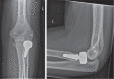

Primary radial head arthroplasty (RHA) produces good or excellent results in approximately 85% of patients. However, complications are not uncommon and have been described in up to 23% of cases.The number of RHA is increasing, and consequently the absolute number of complications is expected to rise as well. The decision on whether to revise or remove the prosthesis seems more likely to depend on the preference of the surgeon or the hospital, rather than on objectifying problems with the prosthesis.The current article presents an algorithm for the work-up and treatment of most complications that can occur following RHA.Five subgroups of problems were identified: osteoarthritis, stiffness, instability, infection and implant-related issues.In short, the preferred treatment depends mainly on the chondral condition and stability of the elbow joint. Cite this article: EFORT Open Rev 2020;5:398-407. DOI: 10.1302/2058-5241.5.190055.